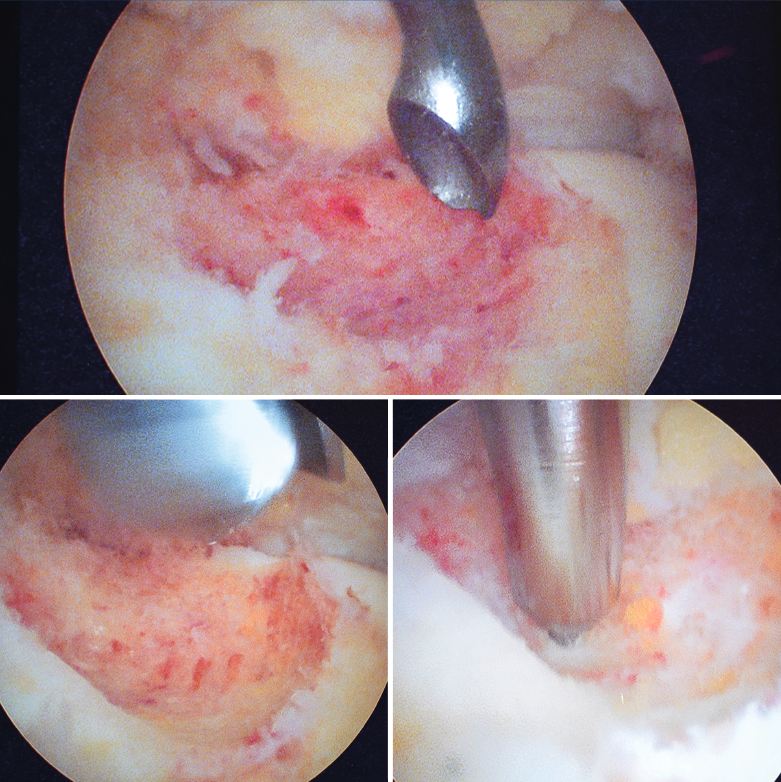

Figura 4. Mediante los portales artroscópicos anteriores habituales (anteromedial y anterolateral) se observa a nivel del cuello del astrágalo anterointerno la característica tumoración de color rojo cereza, que se desbridó con sinoviotomo.

Se visualizó la cúpula astragalina y se observó a nivel del cuello del astrágalo anterointerno una tumoración rojiza con intensa reacción sinovial; se desbridó mediante un sinoviotomo de 4,5 mm (Stryker®, Kalamazoo, Michigan) (Figura 4), tras lo cual se comprobó la inestabilidad de la lesión que se desprendió en bloque (Figura 5), remitiéndose a estudio anatomopatológico.

Posteriormente se realiza curetaje del fondo, eliminando el hueso sobrante en los márgenes, hasta encontrarnos hueso esponjoso de aspecto macroscópico normal, y se realizan perforaciones mediante NanoFx® (Arthrosurface Inc., Bellingham, Massachusetts) (Figura 6).

Figura 6. Curetaje del fondo de la lesión, visualizando hueso esponjoso de aspecto macroscópico normal. Finalmente se realizan nanoperforaciones.